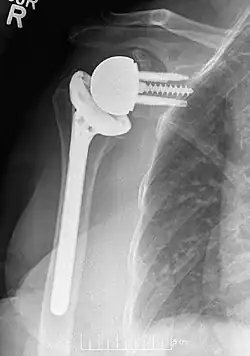

Plain film radiograph in anteroposterior (AP) view of a right shoulder status post reverse shoulder arthroplasty using a prosthesis with a lateralized center of rotation.